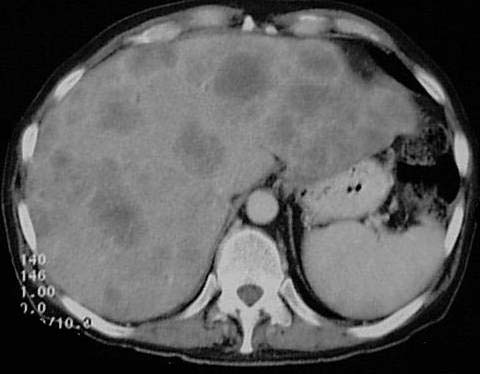

Patient, 55 Jahre alt, Z.n. Colon-Karzinom.

Multiple

weichteildichte Rundherde in

der Leber.

Lebermetastasen bei

bekanntem Colon-Karzinom.